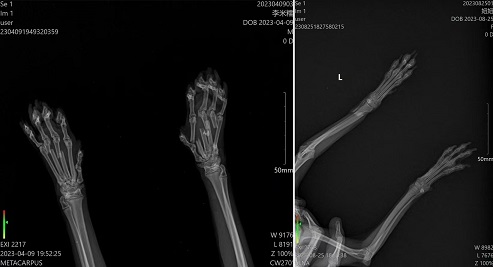

11月6日零基础骨科班现报名人数已满,感谢学员们的信任与选择。已超出本期报名名额的学员安排在本年度12月底一期。本班课程为5天,学员从骨解剖、麻醉、手术通路、骨折骨板、缝合、术后X片及用药全部为实体操作。无围观、无PPT,全天侯手把手教学操作,学后确保独立完成骨科手术。